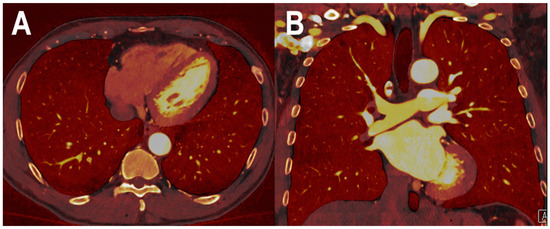

- Yalynska, T.; Polacin, M.; Frauenfelder, T.; Martini, K. Impact of Photon Counting Detector CT Derived Virtual Monoenergetic Images on the Diagnosis of Pulmonary Embolism. Diagnostics 2022, 12, 2715. [Google Scholar] [CrossRef]

- Booij, R.; van der Werf, N.R.; Dijkshoorn, M.L.; van der Lugt, A.; van Straten, M. Assessment of Iodine Contrast-To-Noise Ratio in Virtual Monoenergetic Images Reconstructed from Dual-Source Energy-Integrating CT and Photon-Counting CT Data. Diagnostics 2022, 12, 1467. [Google Scholar] [CrossRef]

| Yalinska et al. [43] | 2022 | In vivo (human) | 8 | Pulmonary vascularization | In multi-energy PCCT images, the best signal was achieved at the lowest VMI (40 keV), while the best visualization of the pulmonary embolism was obtained at 50 keV, due to decreased image noise and hardening artefacts. |

| Kopp et al. [44] | 2022 | In vitro | Pulmonary vascularization | Compared to conventional and HR CT images, PCCT offered an increased spatial resolution and better visibility of lung vessels. | |

| Hagen et al. [18] | 2022 | In vivo (human) | 100 | Pulmonary vascularization | Combining vessel measurements of the aorta and pulmonary vessels resulted in a significantly higher CNR of PCCT compared to EID-CT. |